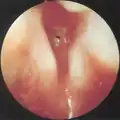

Subglottic stenosis is graded according to the Cotton-Myer classification system from one to four based on the severity of the blockage. Grade 1 is up to 50% obstruction, Grade 2 is 50-70% obstruction, Grade 3 is 70-99% obstruction, and Grade 4 is with no visible lumen.[5]

Grade 1 subglottic stenosis

Grade 2 subglottic stenosis

Grade 3 subglottic stenosis

Grade 4 subglottic stenosis